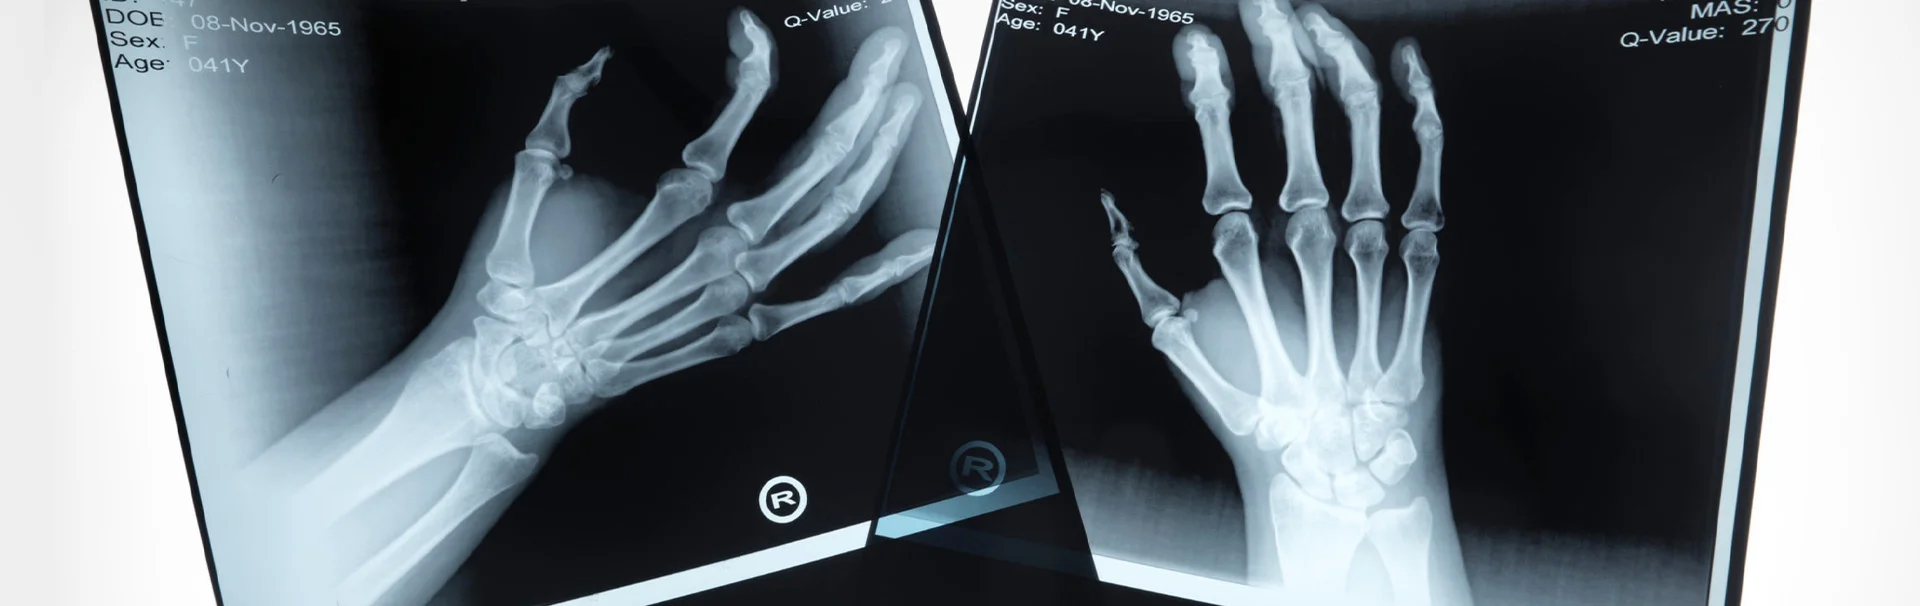

A sajkacsont törését jellemzően fizikális vizsgálat és röntgenfelvétel alapján lehet diagnosztizálni. Ugyanakkor, ha a kéztőcsontok nem mozdultak el a csonttörés közben, az is előfordulhat, hogy a friss sérülés az elesést követő egy héten belül készített röntgenfelvétellel még nem észrevehető. Emiatt, ha az ortopéd szakorvos azt tapasztalja, hogy a páciens kezén, a sajkacsont feletti terület erősen nyomásérzékeny, akkor feltételezi a scaphoideum törését, és gipszeléssel rögzítheti az ízületet. Ezzel megelőzhető a sajkacsonttörés elmozdulása, amely egy nehezebben gyógyítható formája lenne ennek a sérülésnek. Egy vagy két héttel később megismétlik a röntgenfelvételt, és ezen általában már jól kivehető a sajkacsonttörés. Ha ekkor sem egyértelmű a diagnózis, akkor MR-felvétel készítését is elrendelheti az orvos. CT vizsgálattal is diagnosztizálható a sajkacsonttörés, ám ezt a képalkotó eljárást viszonylag ritkán vetik be a sajkacsonttörés diagnosztizálásánál.